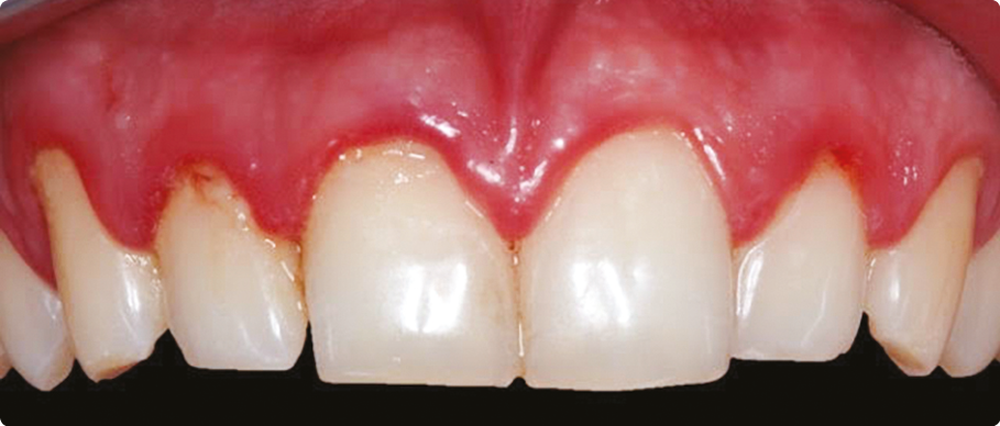

1. Patient de 24 ans en bonne santé, sans médication et sans antécédent de parodontite, présentant un érythème et un œdème gingival.. L’examen de sondage ne révèle aucune PS > 3 mm, le BOP est de 47 %. Il s’agit d’une gingivite généralisée. Le PI est de 53 %, ce qui confirme l’étiologie bactérienne.

• L’examen clinique visuel permet de rechercher les signes cliniques de l’inflammation. Il s’agit d’érythème…